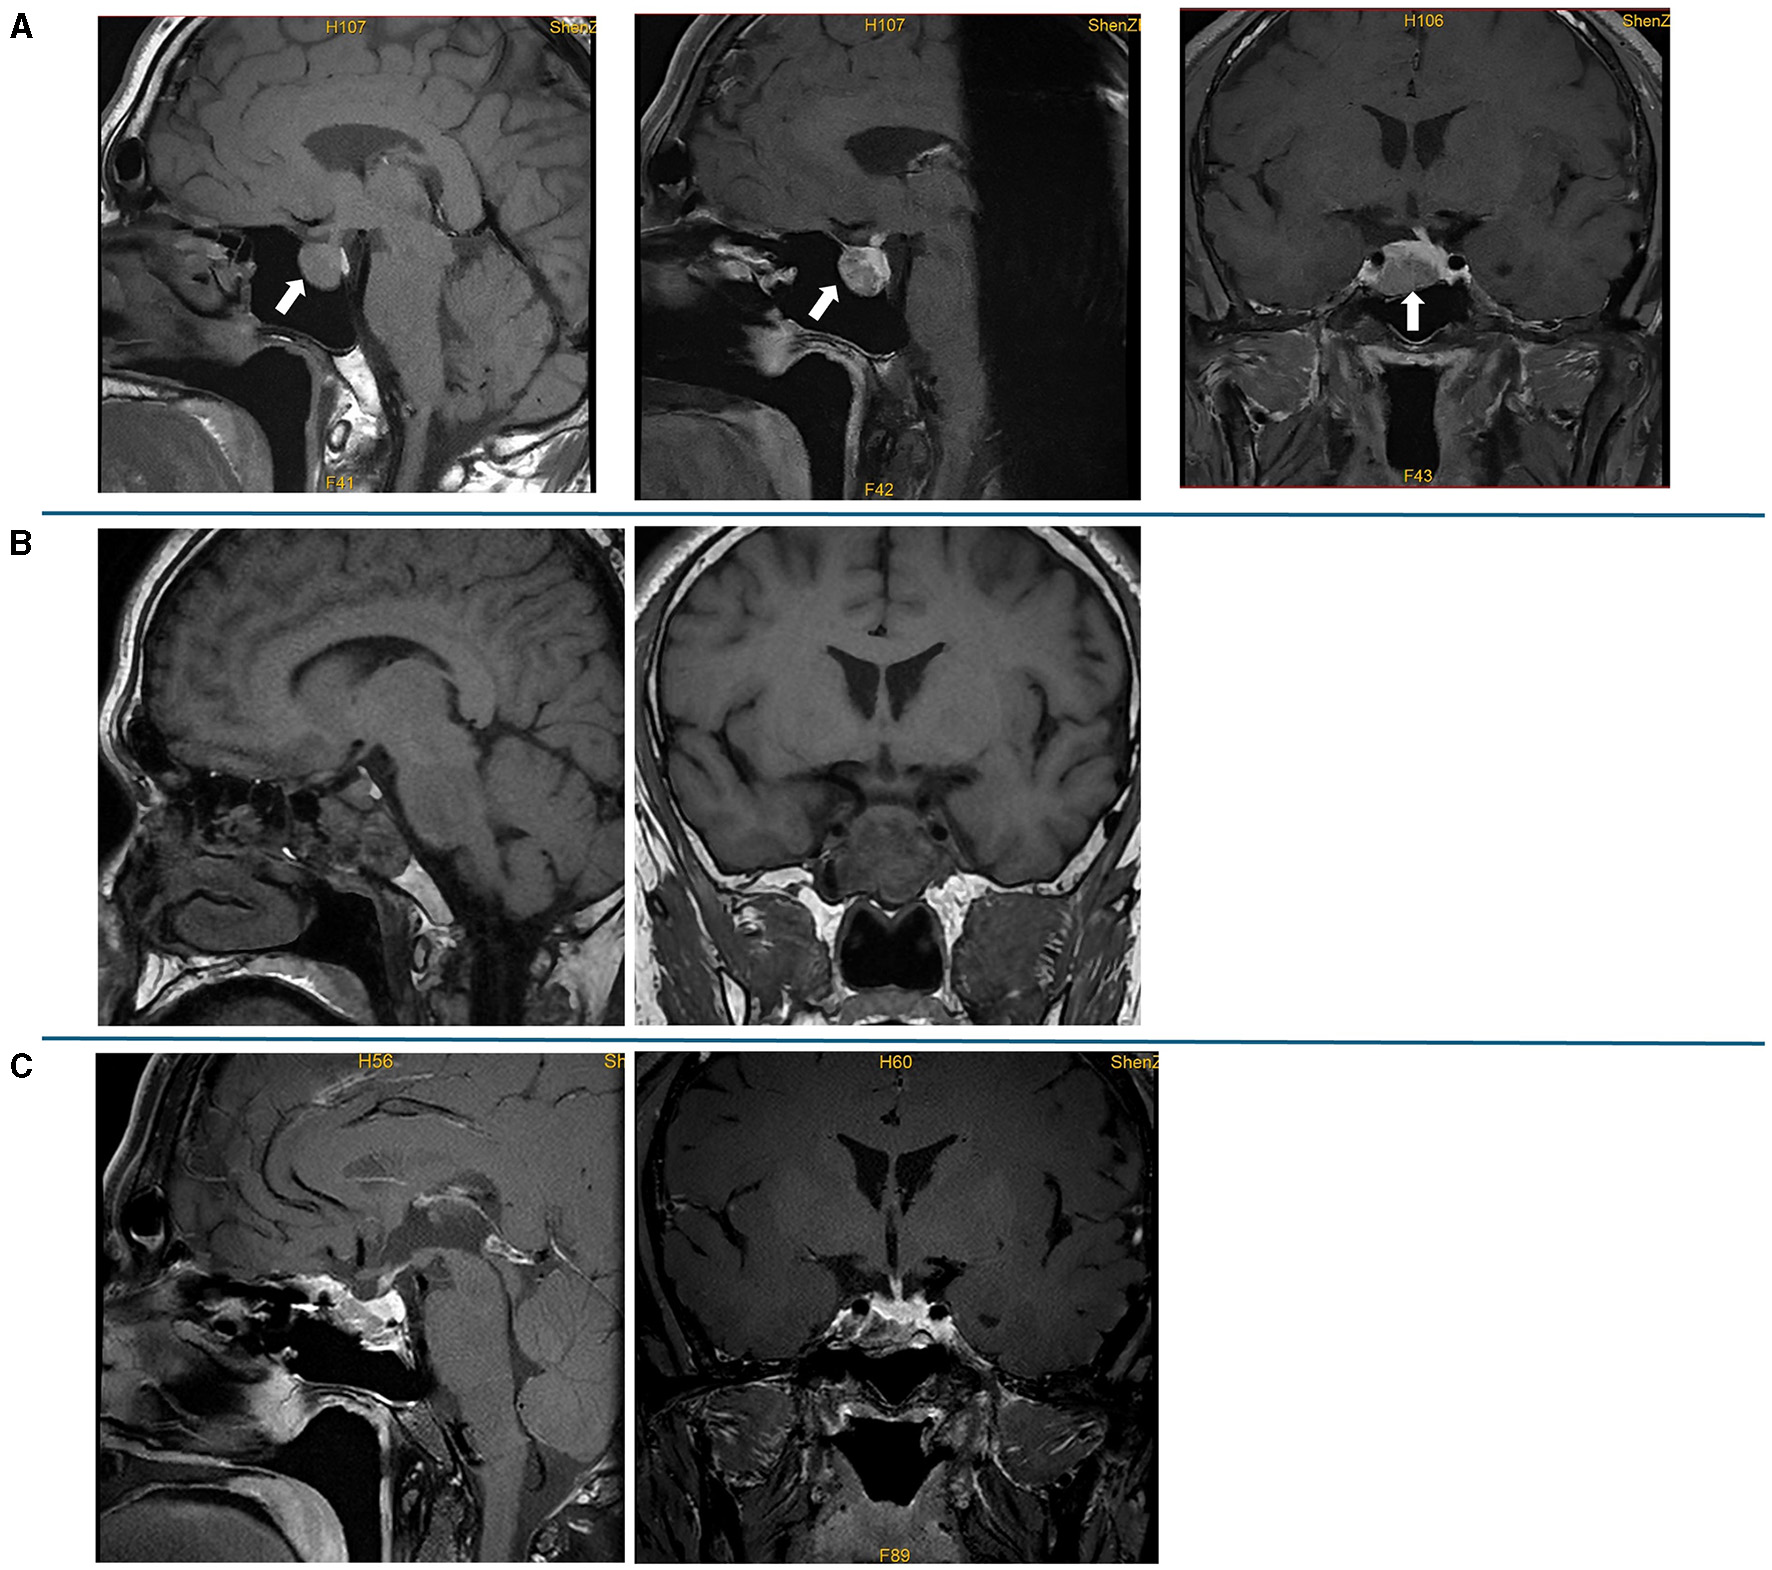

Figure 2

Preoperative and postoperative pituitary MRI. (A) Preoperative plain scan and contrast-enhanced sagittal MRI and contrast-enhanced sagittal and coronal MRI; a lesion (19 mm × 19 mm × 15 mm) in the pituitary fossa is indicated by an arrow. (B) Contrast-enhanced sagittal and coronal MRI on the first day after the surgery; the MRI showed postoperative changes in the pituitary gland, and sphenoid hemorrhagic sinus effusion was considered. (C) Contrast-enhanced sagittal and coronal MRI at 3 months after the surgery, which showed no mass lesion in the sella turcica.

The laboratory tests performed in our hospital showed that his blood, urine, fecal, liver and kidney functions, blood lipids, blood electrolytes, and urine electrolytes were not significantly abnormal. The thyroid function (Figures 1A, B) and thyroid antibodies (Figures 1B, C) were abnormal. Elevated levels of insulin-like growth factor 1 (IGF-1) and procollagen type I N-terminal propeptide (P1NP) were found, while the levels of GH, sex hormones, and sex hormone-binding globulin (SHBG) were in the normal range (Table 1). The blood cortisol and adrenocorticotropic hormone (ACTH) levels were in the normal range (Table 1). The chest X-ray findings were normal. The ultrasound showed heterogeneous echogenicity of the thyroid gland. The thyroid emission computed tomography (ECT) showed a slightly enlarged thyroid, which was normal in shape and position, and the distribution of the imaging agent was non-uniform. No obvious concentrated, sparse, or defective images of the localized imaging agents were found in the thyroid gland. The contrast-enhanced MRI of the pituitary gland showed enlargement of the pituitary fossa, with a mass (19 mm × 19 mm × 15 mm) of irregular abnormal signals within the region; the lesion grew from the sellar region to the suprasellar and parasellar regions, with depression in the sellar floor. The optic chiasm was compressed with mild elevation, with an unclear structure of the pituitary stalk and involvement of the right cavernous sinus; and it was in contact with the inner edge of the right internal carotid artery, without obvious wrapping. This indicated a macroadenoma (Figure 2A). The ophthalmic visual field examination showed no obvious abnormality.

The levels of free triiodothyronine (FT3) and free thyroxine (FT4) at 1 and 2 months after the surgery reduced; however, they were still in abnormal ranges (Figure 1A). The thyroid antibodies were still positive at 1 month after the surgery (Figures 1B, C). The levels of IGF-1 (Figure 1D) and SHBG (Table 1) were downregulated, and the P1NP level reduced to 86.30 ng/ml (9.06~76.24 ng/ml), 1 month after the surgery. The levels of sex hormones, cortisol, and ACTH at follow-up were normal. The MRI showed no mass lesion in the sella turcica at 3 (Figure 2C), 8, and 11 months after the surgery.